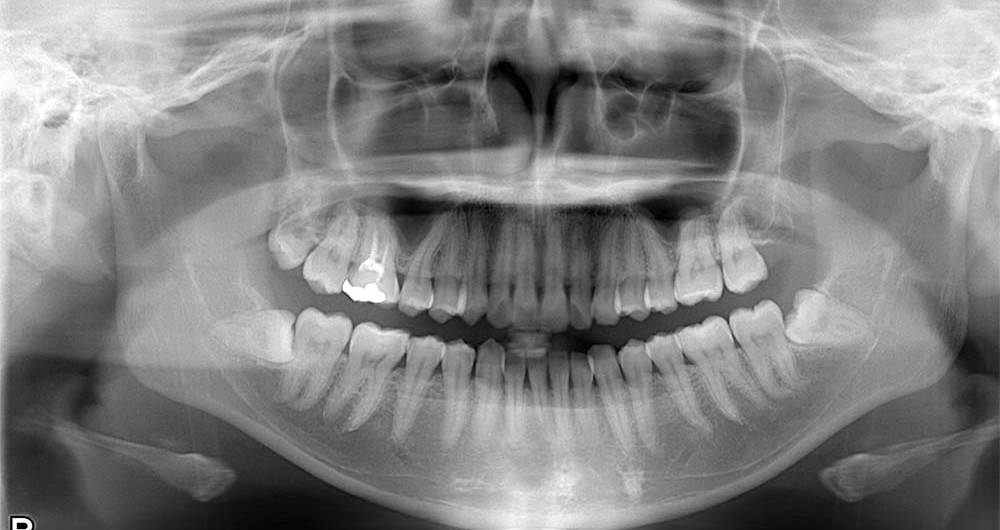

40代男性

ケース1:左下の歯が痛い

親知らずが隣の歯と重なり虫歯になった患者さんです。

他県の歯科医院より紹介頂き受診されました。初診の当日に処置を行っています。

歯の頭の部分を削って抜きました。切開は行っていませんが2糸縫って終わっています。

術後は紹介先で経過を診て頂いていますが、少しの腫れはあったようですがその他は特に問題はなかったようです。

- 所要時間

- 15分程度

- 費用

- ¥9,000(健康保険内)